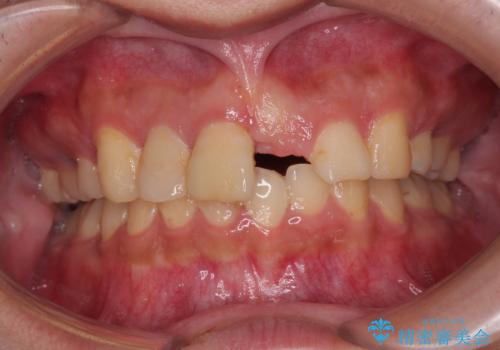

セラミックで自然な口元となり、視線が集まっていたことも気にならなくなったとのことでした。